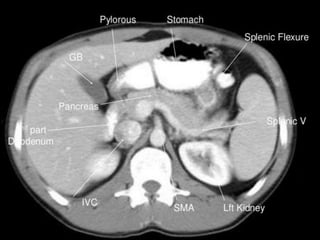

CT cross sectional

anatomy.

Ct abdominal ………………………………………………………...pdf